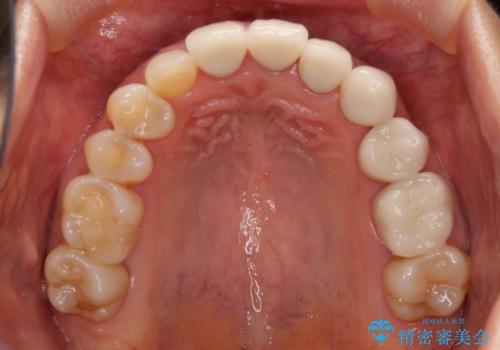

歯肉レベルを調整するために歯周外科処置をおこない、その後にオールセラミッククラウンにて補綴することとしました。

処置後の痛みはあまり気にならず、歯肉位置の左右差もほとんどなくなり、患者様には大変満足していただきました。